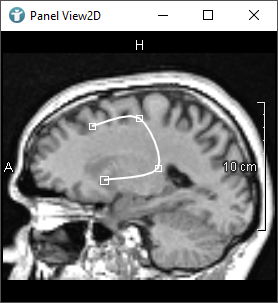

In the next image, you can see a rectangular shaped CSO. The pink circles you can see are called Seed Points.

Seed Points define the shape of the CSO. In the case of a rectangle, you need four Seed Points forming the corners to define the whole rectangle.

The points forming the blue lines are called Path Points.

The Path Points form the connection between the Seed Points whereby contour objects (CSOs) are generated. CSOs are often closed, but do not need to be.